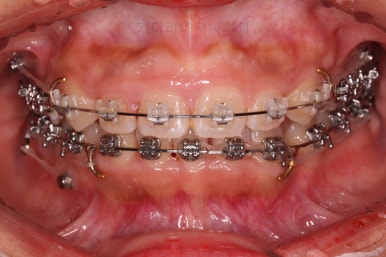

오늘 소개해 드릴 환자분은 아래 앞니가 하나 없는 결손치아, 그로 인해서 윗니 앞니가 뒤로 굽어 들어오는 "옥니", 그로 인해 위아래 앞니가 많이 겹치는 과개교합 및 잇몸웃음(거미스마일)이 나타나는 복합적인 문제가 있는 분이셨습니다.

사용한 장치 : 자가결찰 메탈 + 세라믹 복합(엠파워 메탈, Empower metal + 세라믹) + 미니스크류

우선 윗니부터 가지런하게 해줍니다.

앞니쪽에는 미니스크류를 식립했는데요.

과개교합 개선, 교합 개선, 거미스마일(잇몸웃음) 개선 등 여러 가지 목적을 동시에 달성할 수 있어요.

윗니가 어느 정도 가지런해지면 아랫니도 장치가 들어갑니다.

과개교합이 어느 정도 개선이 되어서 아래 앞니가 서서히 보이기 시작하네요.

이번 부산옥니교정 환자분이 선택하신 장치는 엠파워인데 윗니는 덜 보이는 세라믹, 아랫니는 메탈입니다.

같은 엠파워 장치이기 때문에 이렇게 섞어 써도 문제가 전혀 없는데요.

흔히 아시는 클리피씨로 하자면 윗니는 클리피씨 + 아랫니는 클리피엠(M)인 셈이죠.

윗니는 세람기으로 해서 심미성을 강조하고 아랫니는 좀 더 부피가 작고 강하여 과개교합 교정에 유리하며 저렴하기도 한 메탈로 했습니다.

장치 부착 직후의 모습입니다.